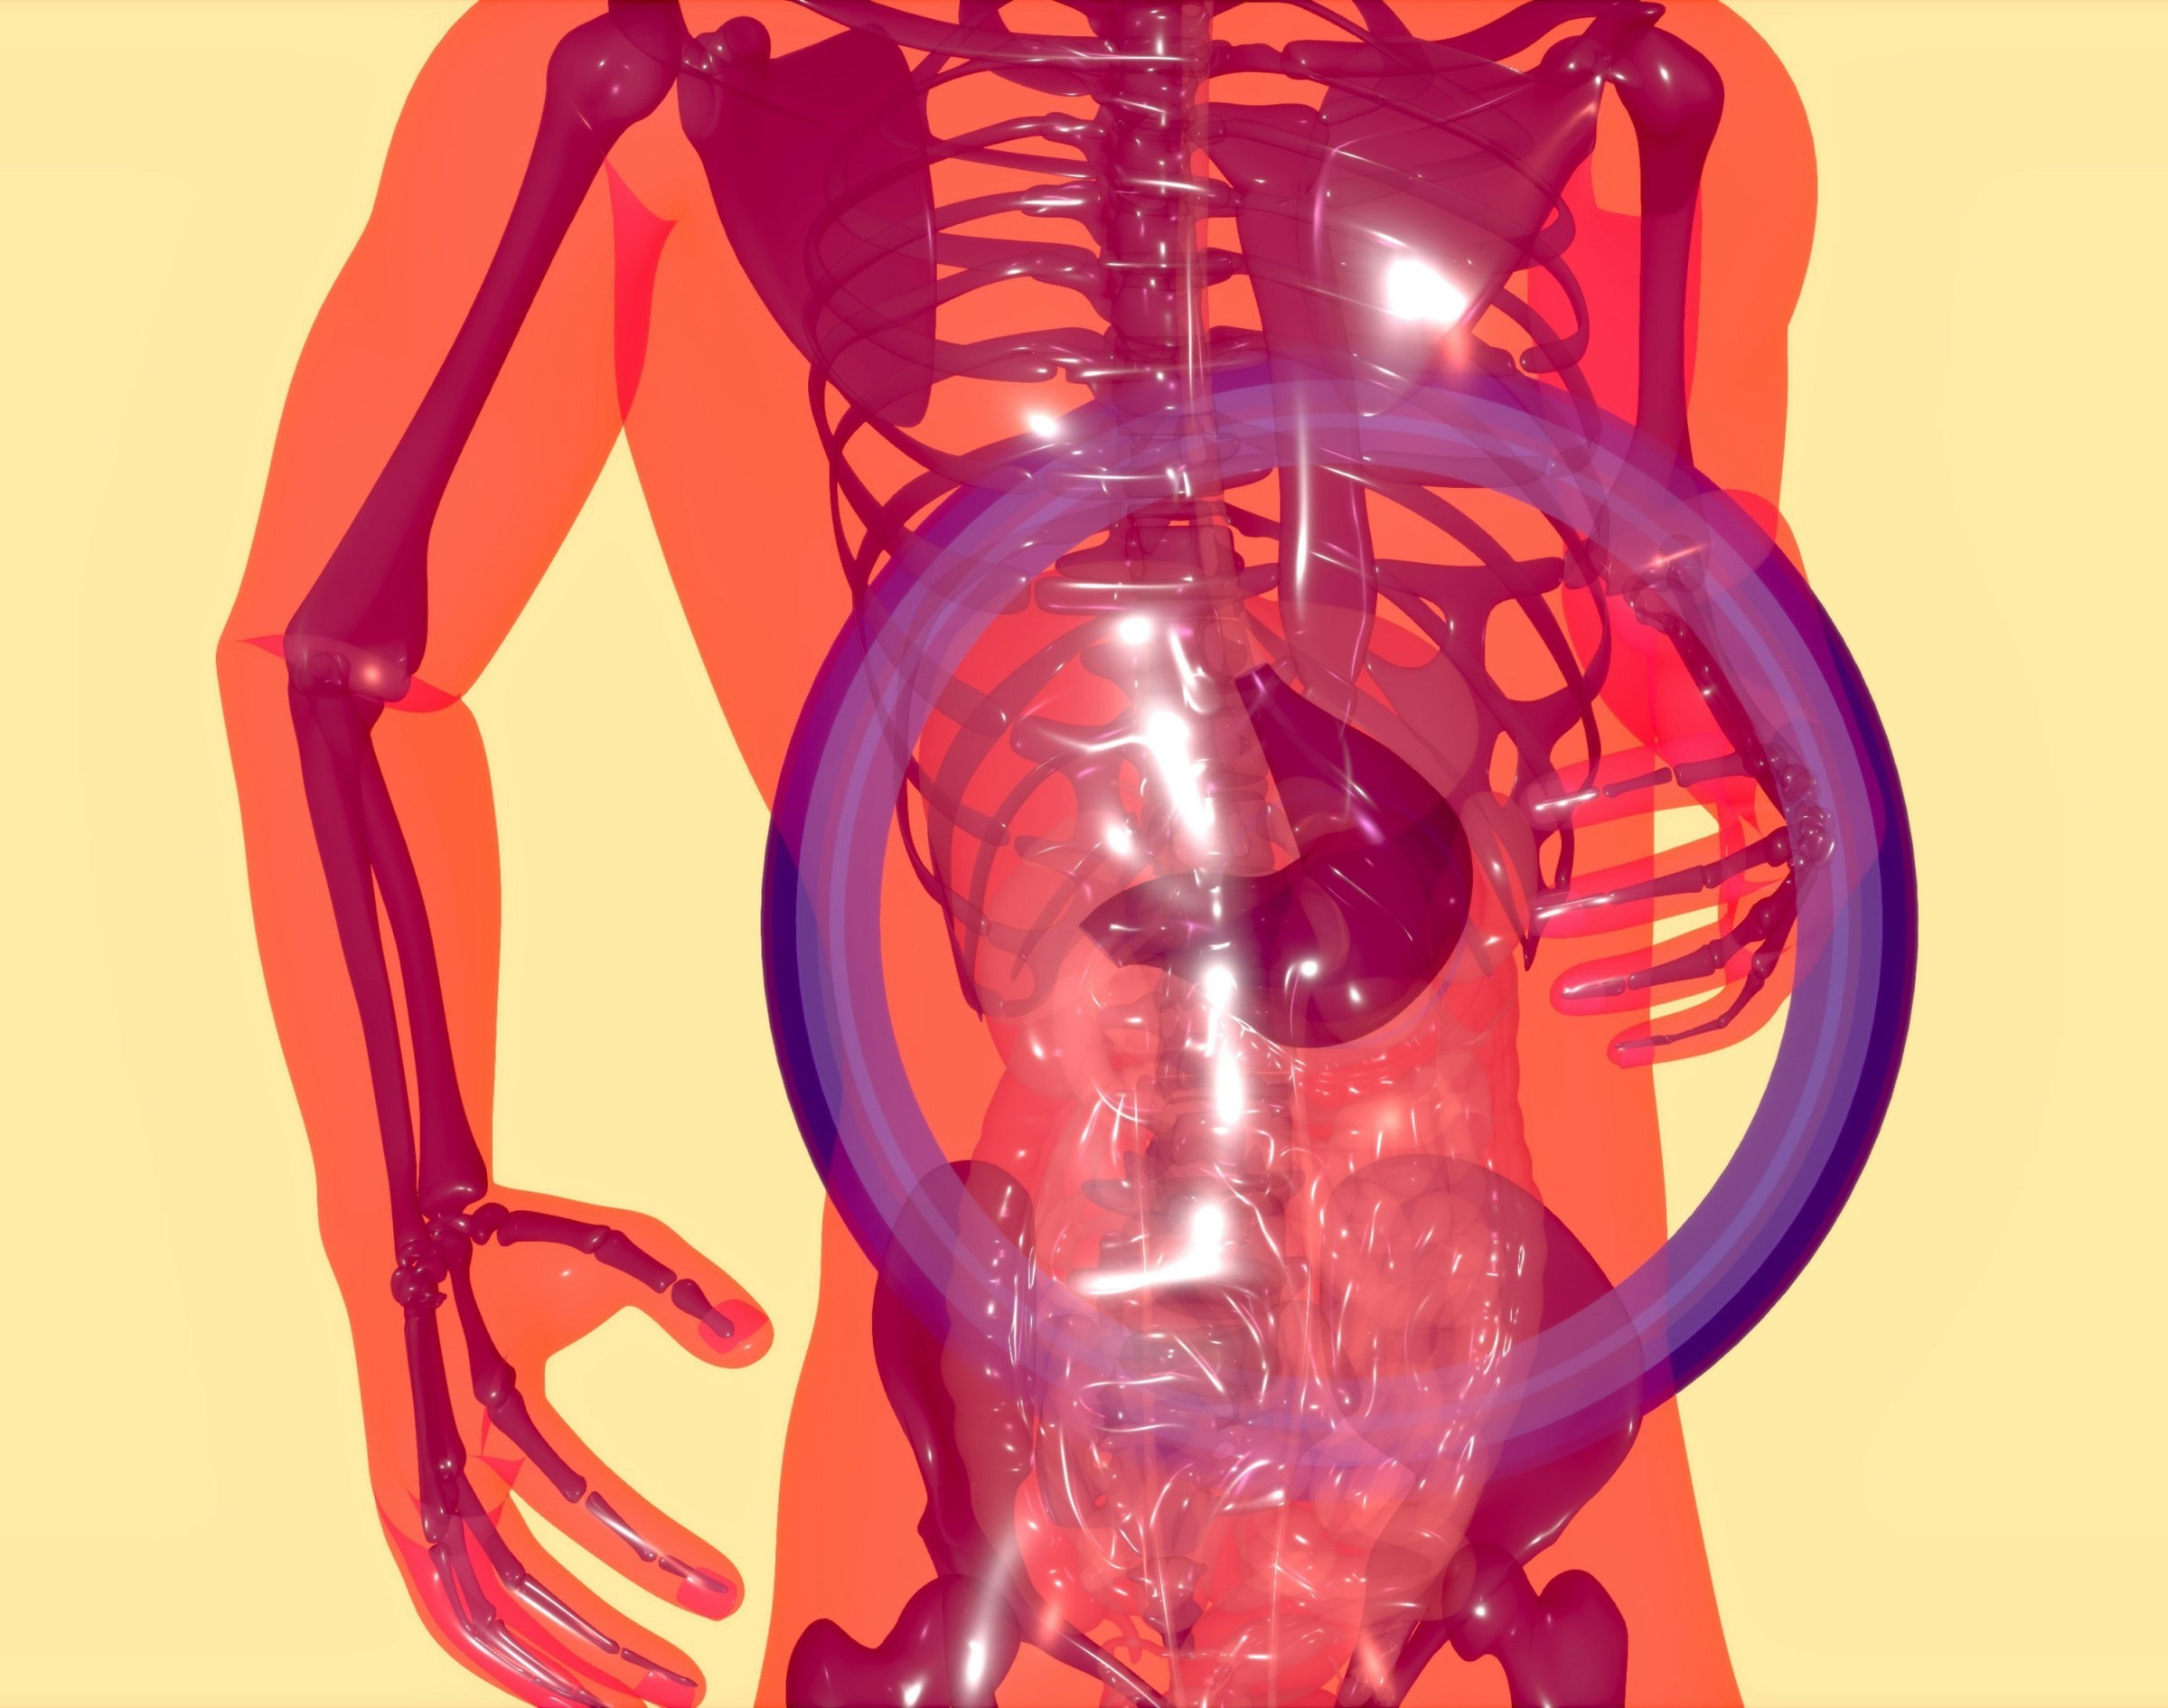

Ganzheitliche Darmtherapie

Die Therapie bezieht sich auf verschiedene Ansätze zur Behandlung von Störungen im Verdauungssystem, wie zum Beispiel Störungen des Mikrobioms/Darmflora (verstärkt nach Antibiotikaeinnahme), Parasitenbildung wie Pilze, ausschließliche symptomatische Beschwerden wie das Reizdarmsyndrom, Störungen der Verdauungsorgane (Leber, Bauchspeicheldrüse, Galle, Magen) aber auch Nahrungsmittelunverträglichkeiten oder Allergien.

Die Therapie ist optimal anzusetzen anhand eines Stuhlbefundes und evtl. eines Blutbefundes, den ich im Labor veranlassen kann. Die Therapie umfasst nach Bedarf und individuell eine s.g. Entgiftung, Ernährungsberatung, eine Pro- und Präbiotikagabe zum Aufbau des Mikrobioms, eine Phytotherapie, Mikronährstoffbehandlungen und Weiteres. Oftmals treffe ich hier Patienten mit einem hohen Leidensdruck an. Als Beispiel sind hier Menschen mit der „Volkskrankheit“ Reizdarmsyndrom zu nennen, welches in allen Altersklassen vertreten ist. Schon das Verlassen der Wohnung stellt diese Menschen häufig vor grosse Herausforderungen, da sie unter permanenten Stuhldrang oder Bauchkrämpfen leiden. Leider ist die in der Werbung empfohlenen Therapie häufig nicht zielführend und eine genauere Diagnostik zum Ausschluss weiterer Ursachen, wie o.g., ist nicht erfolgt.

Indikationen zur Behandlung können einfache Verdauungsstörungen sein wie Durchfälle, Verstopfung oder Übergewicht, Fettleber, Allgemeinsymptome wie Müdigkeit, Schwindel, befundlose unklare Gelenk-, Knochen- und Muskelschmerzen aber auch Erkrankungen wie Allergien, Akne, Asthma bronchiale, Neurodermitis, Fatique-Syndrom, Depressionen und mehr.